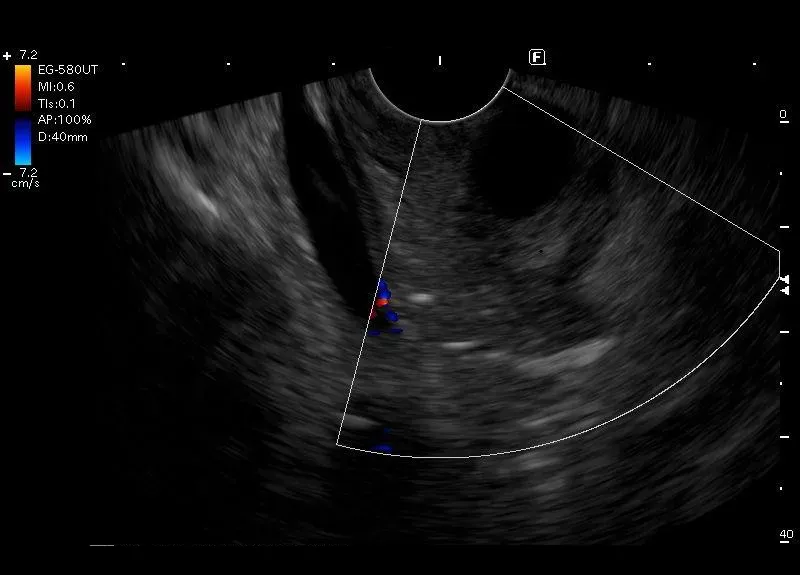

Śródścienna,10 milimetrowa torbiel w pogrubiałej do 15 mm ścianie

dwunastnicy - w wybranym przypadku element obrazu odpowiadającego zapaleniu

bruzdy.